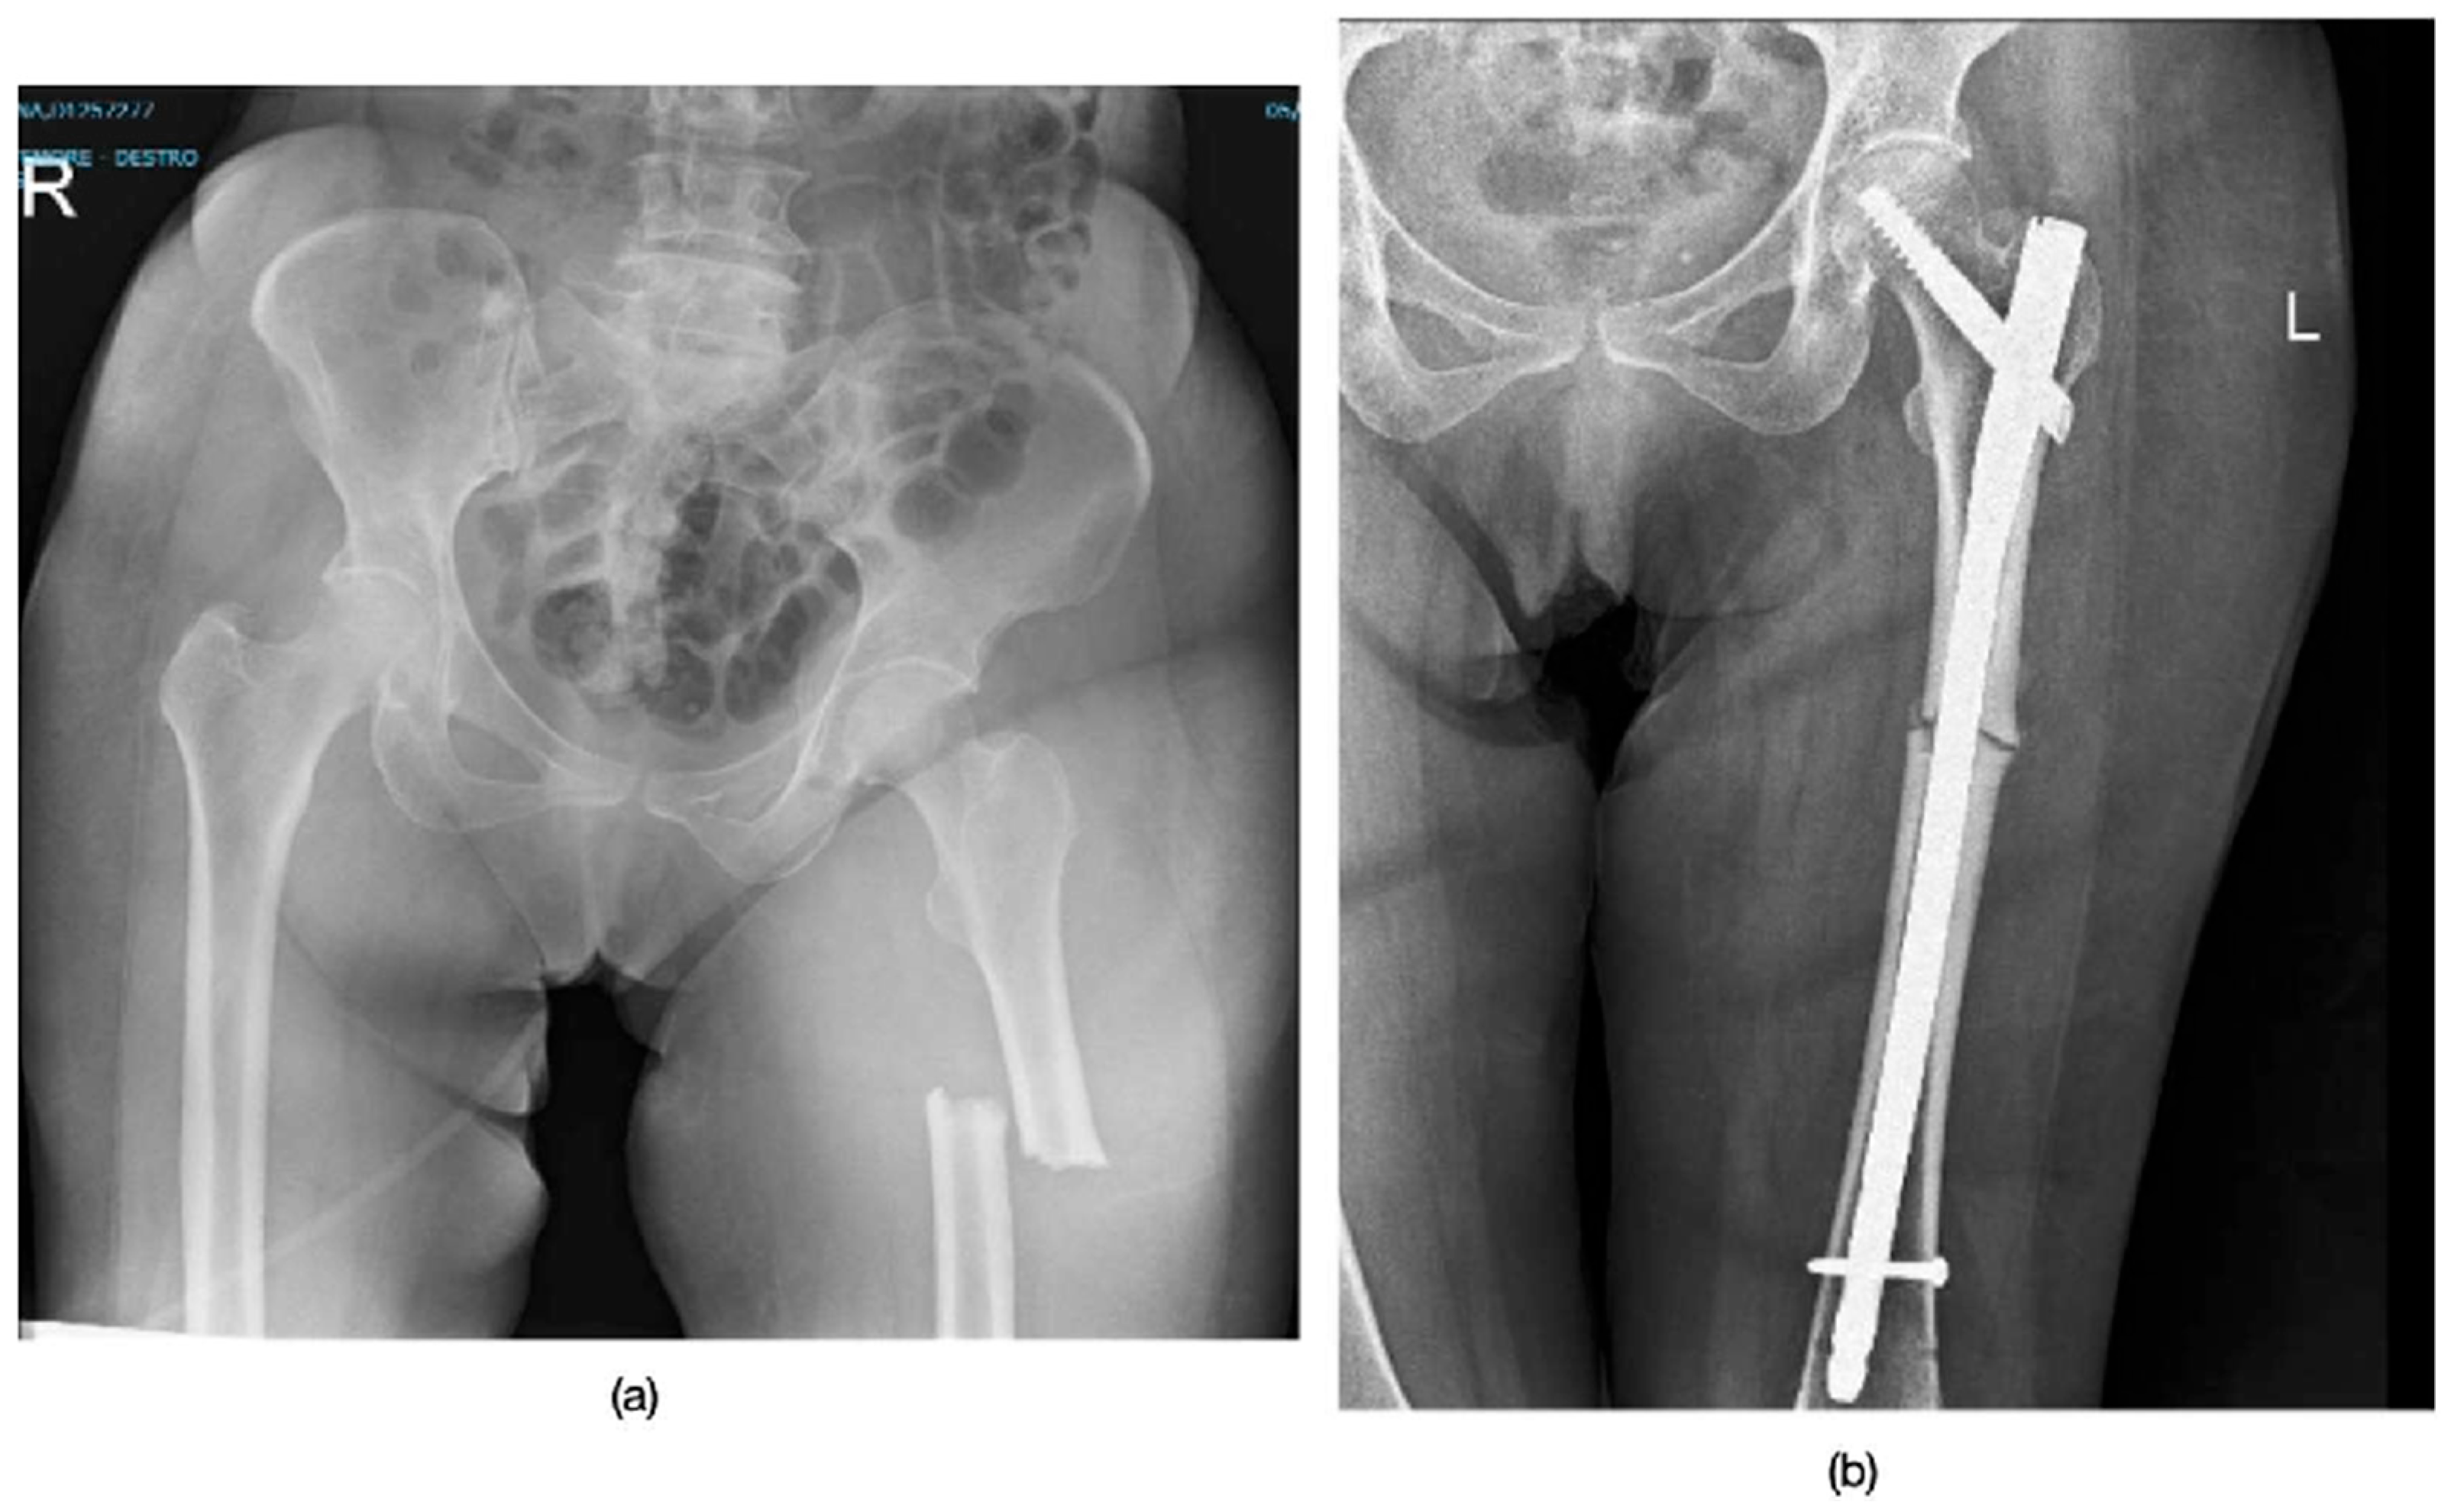

3.1. Patient Demographics and Fracture Characteristics

3.2. Treatment and Healing Process

| SEX | BMI | Fracture Type | Side Fracture | Time of Surgery | ASA Score | |

|---|---|---|---|---|---|---|

| Patient 1 | F | 20 | Subtrochanteric | Left | 48 h | 2 |

| Patient 2 | F | 23 | Mid-third diaphysis | Right | 48 h | 2 |

| Patient 3 | F | 31 | Subtrochanteric | Left | 24 h | 2 |

| Patient 4 | F | 22 | Mid-third diaphysis | Right | 48 h | 3 |

| Patient 5 | F | 26 | Mid-third diaphysis | Right | 72 h | 2 |

| Patient 6 | F | 18.5 | Mid-third diaphysis | Right | 48 h | 3 |

| Mean Age | Involved Side | Localization | Time of Use of Bisphosphonates | Surgical Treatment | Pseudoarthrosis |

|---|---|---|---|---|---|

| 70.3 ± 6.5 y | 4 Right, 2 Left | 2 subtrochanteric 4 mid-diaphyseal | 7.3 ± 1.5 y | long intramedullary nail | 0% |